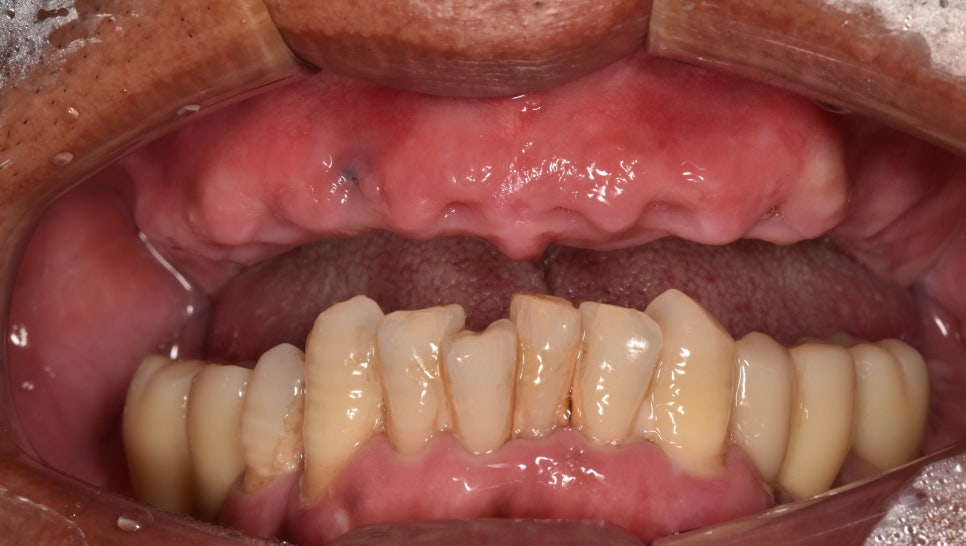

오늘은 상악(위턱)

치아가 하나도 없어서

일상생활에 큰 고통을 겪고 계셨던

환자 이야기를 들려드릴까 하는데요.

다른 곳에서 임플란트 시술 을 한 번 받았으나

치은(잇몸) 밖에서 다 보이는 상태였습니다.

서둘러 구강 검진을 시행한 결과,

위턱 치아가 전부 발치되어 있었습니다.

그뿐만 아니라 환자께서 말씀하셨던

픽스처가 외부로 보이고 있었는데요.

하악(아래턱) 치아를 살펴보니

이미 임플란트 시술 을 받으셨는데요.

이와 달리 앞니는

아무런 처치를 받지 않아

정출과 치석이 발생하여

교합에 방해를 주고 있었습니다.